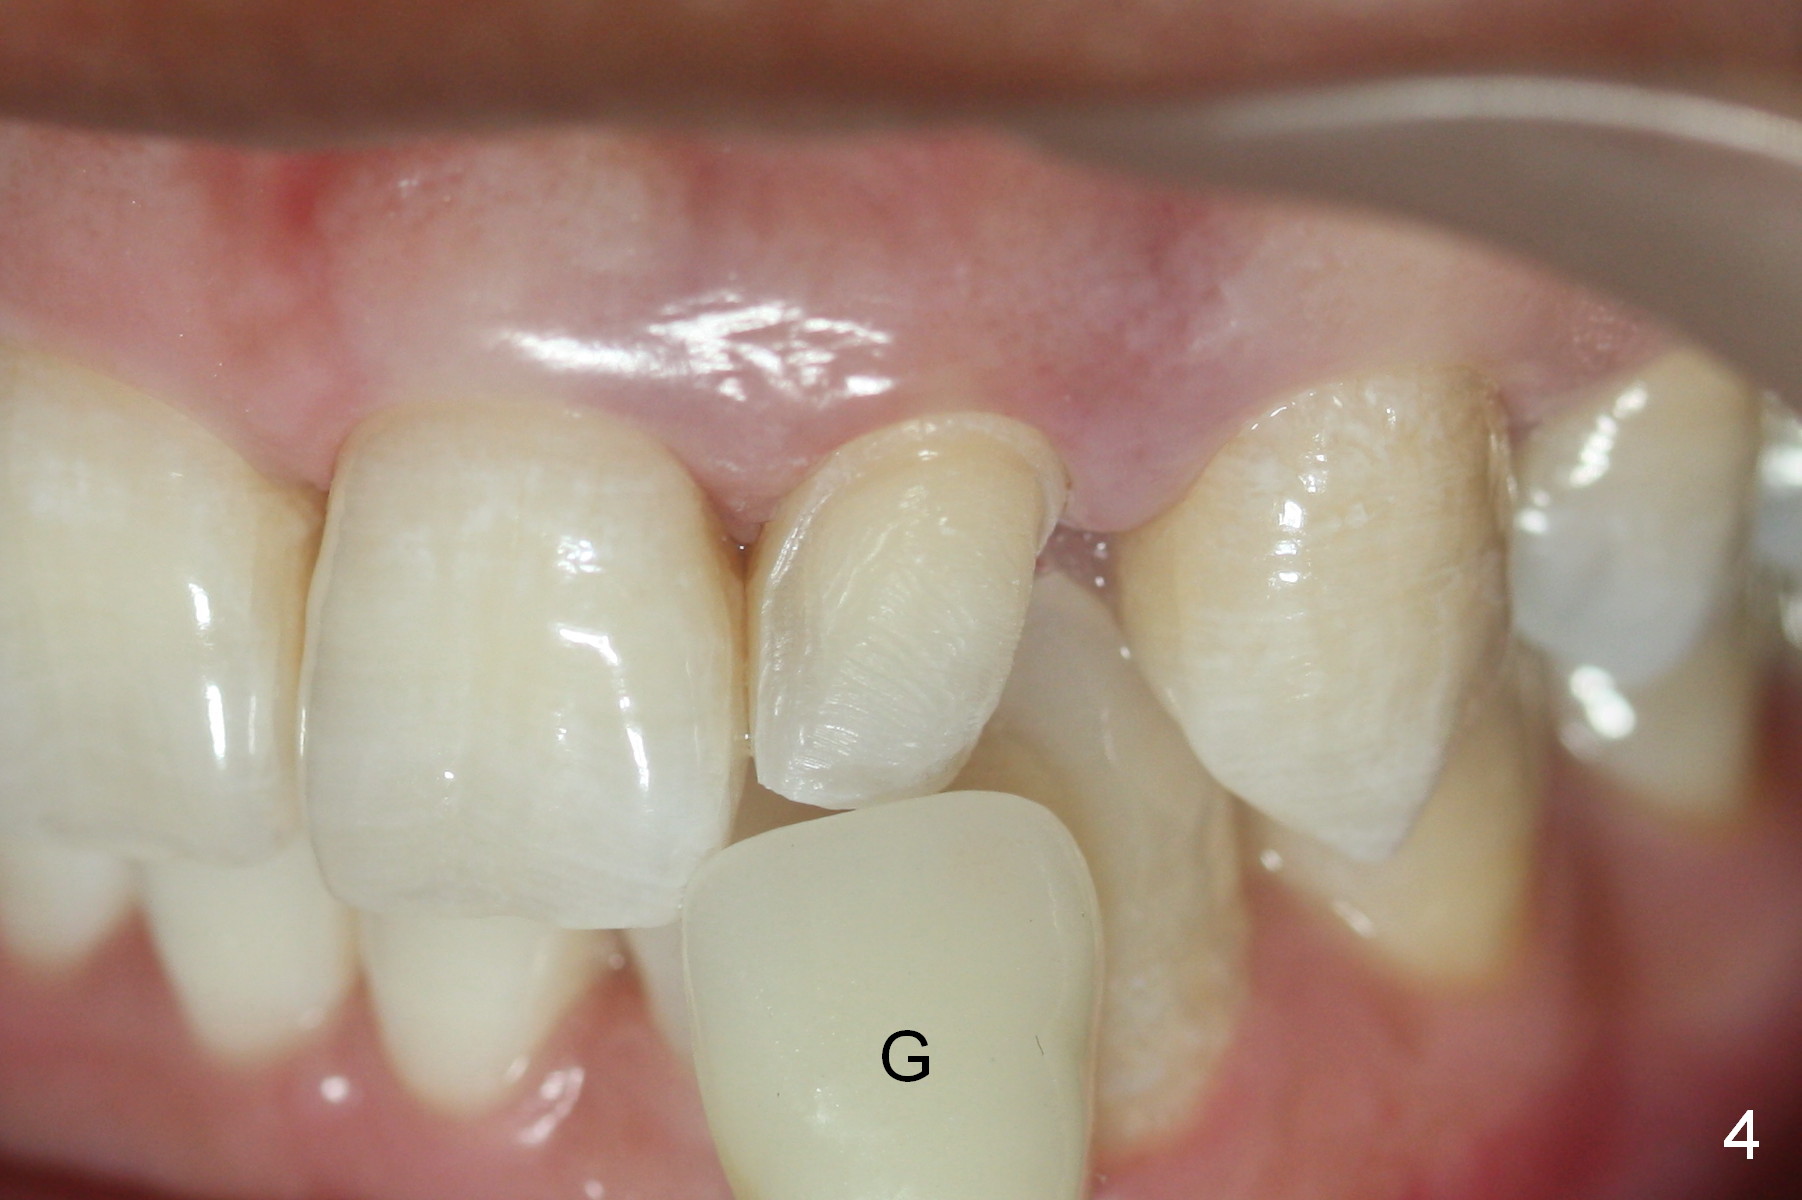

| Middle |

A 36-year-old man has 2 small, congenitally deformed lateral incisors (peg laterals, Fig.1,2 *). After discussion, we choose porcelain veneers for cosmetic makeup. The teeth need minor shaving (Fig.3,4); right colors are being selected with a shade guide (Fig.4: G). The shaving is so conservative that there is no pain during the procedure and there is no need to make temporary veneers. One to 2 weeks later, porcelain veneers are cemented (Fig.5,6). The patient is satisfied.